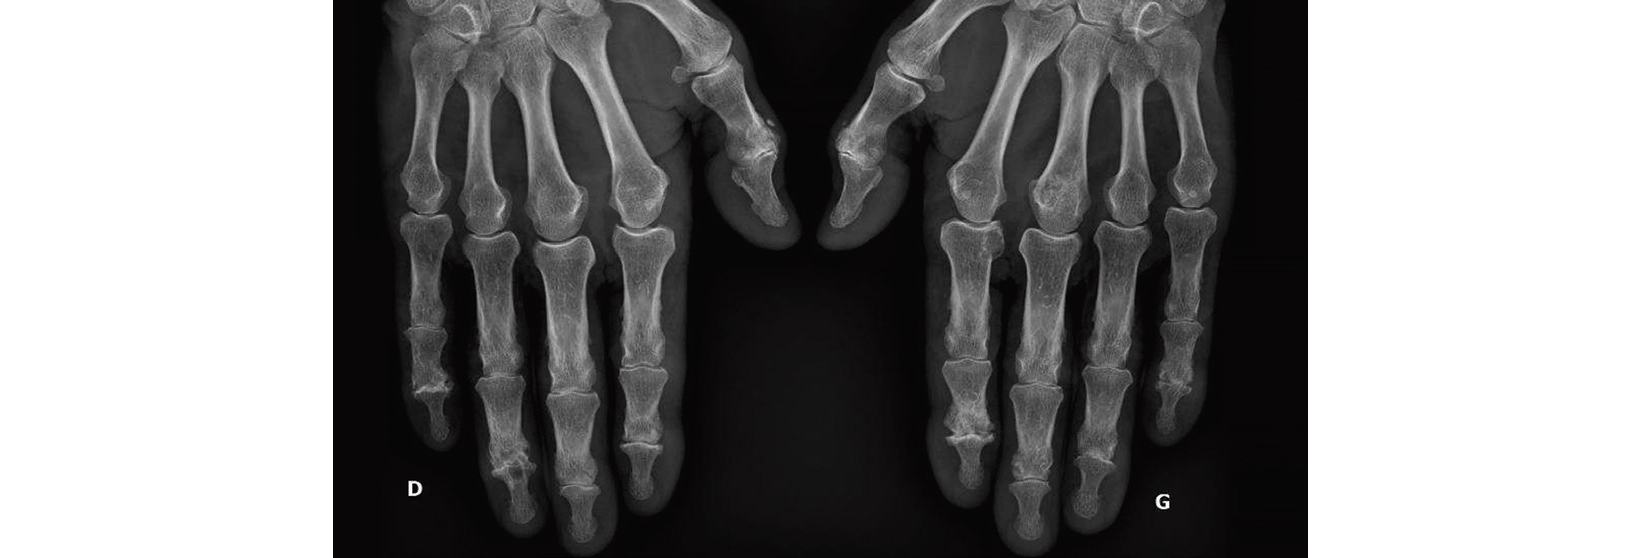

Arthrose digitale

L'arthrose digitale (plus fréquente aux interphalangiennes distales qu'aux interphalangiennes proximales) est la plus courante des localisations arthrosiques avec une prédominance féminine, elle s'associe souvent aux autres localisations de l'arthrose notamment la gonarthrose.

Le plus souvent bilatérale mais la main dominante est davantage symptomatique. La plainte du patient est liée à la douleur, à la gêne fonctionnelle et esthétique en raison des déformations.

Le diagnostic est clinique avec douleur et déformation des interphalangiennes et pouvant être visibles des nodules d'Heberden aux IPD ou de Bouchard aux IPP. Les radiographies ne sont pas nécessaires au diagnostic.

Arthrose digitale chez un patient de 77 ans avec la radiographie

une arthrose prédominante aux interphalangiennes distales avec

présence de pincement articulaire, condensation de l'os

sous-chondral et érosions.